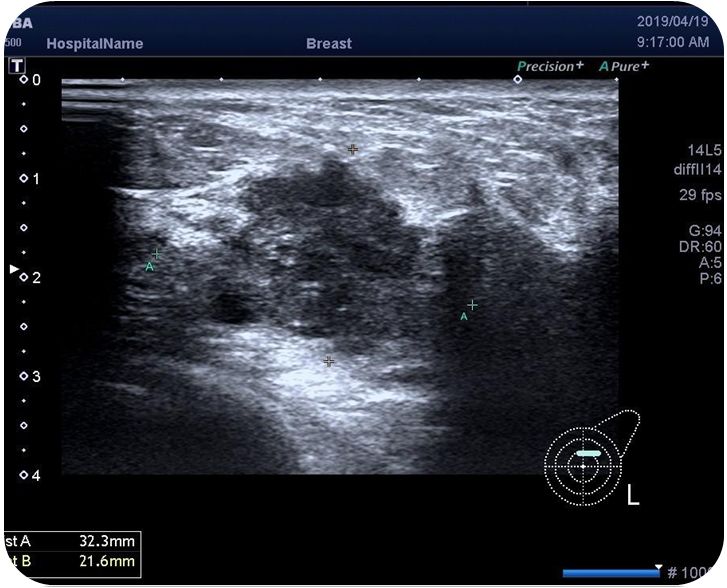

乳腺超声:左乳上象限探及低回声结节,大小约3.2*2.2*3.8cm,边界不清,形态不规则,可见点状强回声,右乳未见异常肿块回声。左侧腋窝探及一皮髓质可辨的淋巴结。